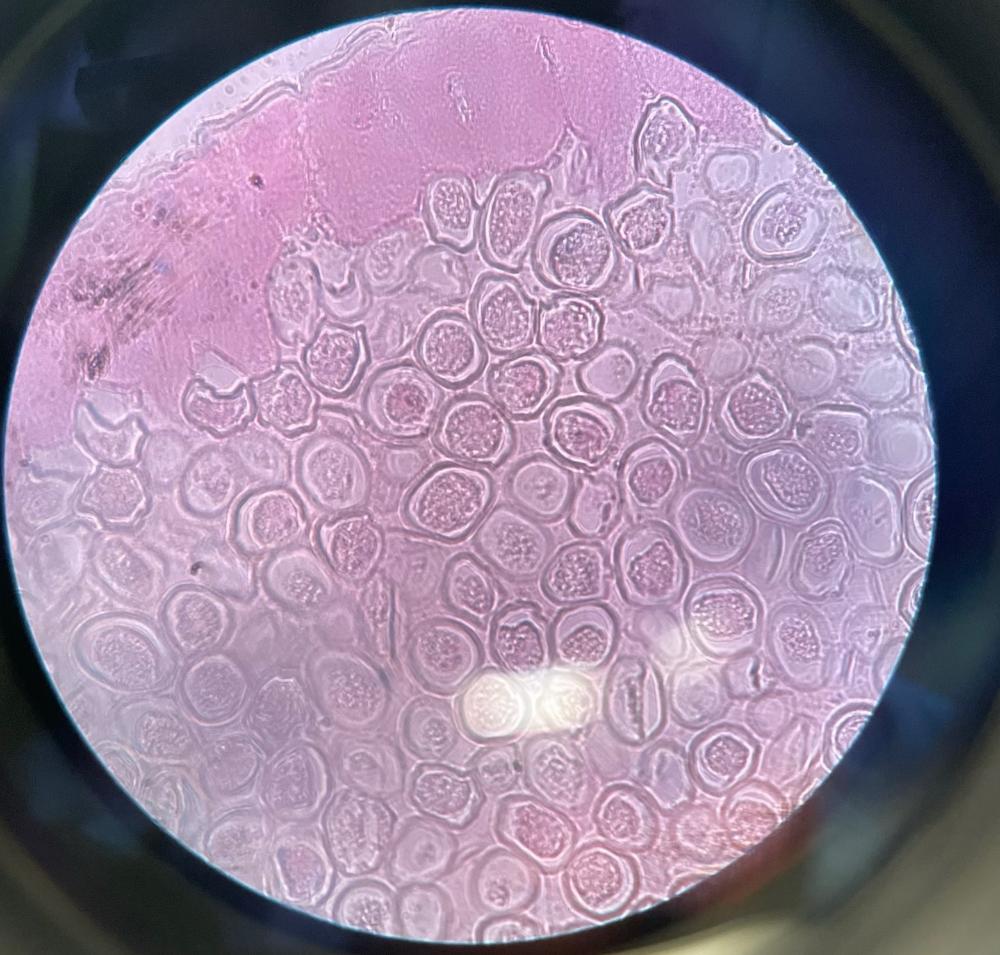

Candida